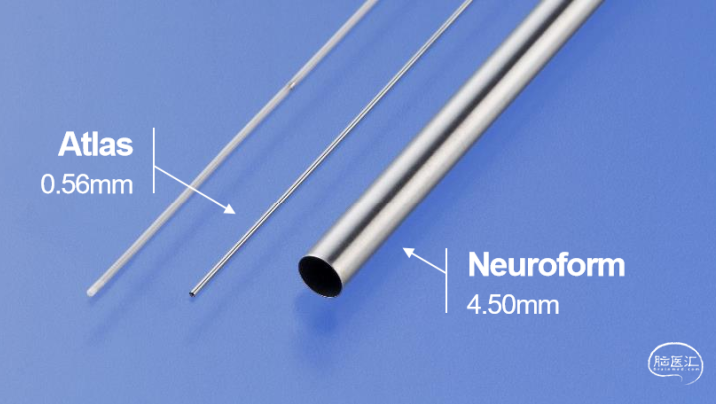

Atlas支架仅需0.0165"的SL-10微导管输送,支架释放后该微导管可调整位置继续充当填塞弹簧圈的输送微导管,一管多用,切换灵活,省时降费。

更细的输送系统

全尺寸通过SL-10和XT-17微导管释放。